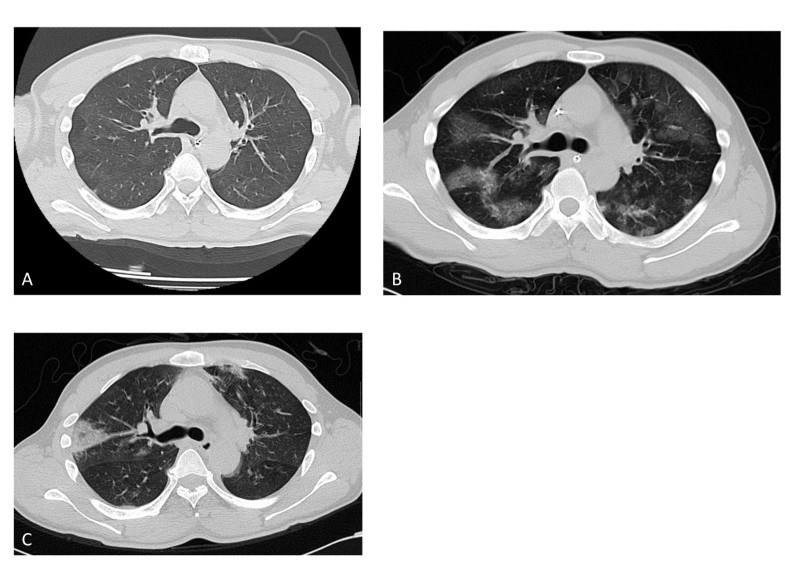

From ccforum.biomedcentral.com

Chest computed tomography performed on admission helps predict the Smoke Inhalation Pneumonitis Inhalation injury is damage to the respiratory tract or lung tissue from heat, smoke, or chemical irritants. Learn what to look for and how to treat these patients quickly and efficiently. Smoke inhalation is a primary cause of mortality in patients exposed to fire. Smoke inhalation injury can be defined as damage caused by breathing in harmful gases, vapours, and. Smoke Inhalation Pneumonitis.